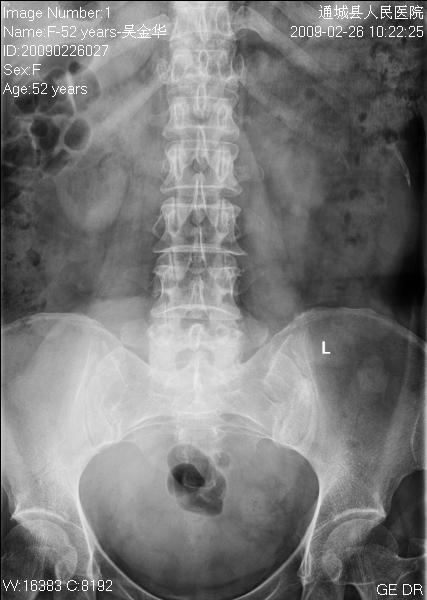

女性,52岁,腰痛二年余。

临床诊断:腰椎退行变。

平片仅能提示退变

1)腰椎退行改变。2)考虑盆腔巨大占位性病变;建议行进一步检查。

1)腰椎退行改变。2)考虑腹盆腔巨大占位性病变(其大部边缘清楚)考虑:来源于卵巢占位性病变可能,建议mri检查.

退变,下腹部椭圆形密度增高影是什么呀?建议行ct检查一下。